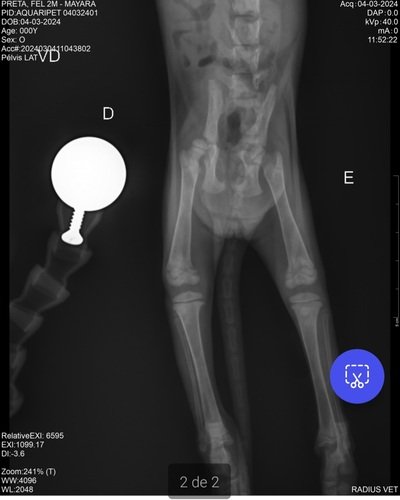

Oi pessoal, espero que estejam bem. Domingo a noite quando voltava para casa vi um motociclista atropelar essa bebezinha, ele não prestou socorro e eu não poderia deixar ela lá desse jeito. Levei ela ao veterinário e preciso de ajuda! Ela está com diversas fraturas graves, luxação no joelho, fratura acetabular e hérnia diafragmática - tudo devido ao impacto do atropelamento. Se você puder auxiliar com qualquer valor na vaquinha online ou entre em contato comigo para mais informações. Após ela se recuperar, também precisaremos achar um lar, pois eu não consigo ter mais 1 gatinho. Agradeço muito a atenção e se o seu coração for tocado e for possível ajudar essa pequena, agradecemos imensamente. Um lar com gatinhos é um lar com mais amor 🥰 segue imagens da gatinha e exames, bem como valor da clínica Aquaripet até o momento